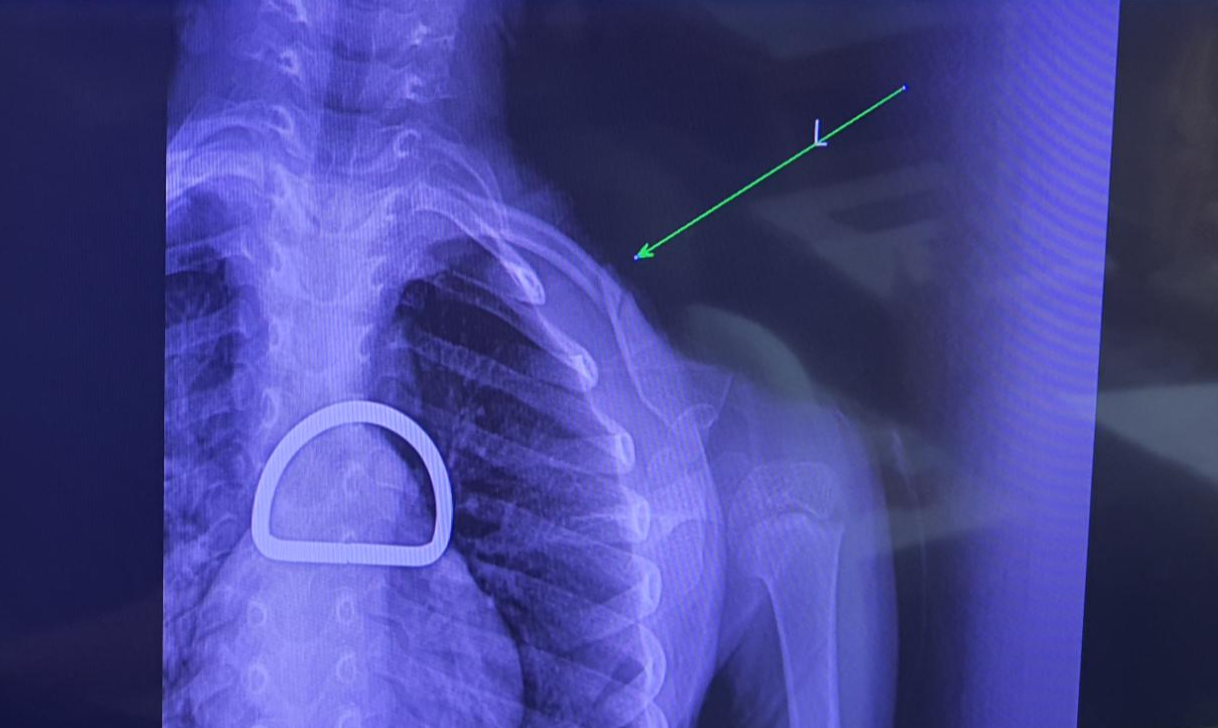

의사 선생님이 깁스를 착용시켜 주시고

자세를 조정한 후에 다시 엑스레이를 찍어

뼈가 바르게 붙을 수 있는 자세로

정확하게 고정되었는지를 확인합니다.

위의 엑스레이 사진에서

척추 부분에 보이는 선명한 반원 모양은

자세교정 깁스에 달려있는 플라스틱 고리입니다.

약 4주 뒤에 다시 병원에서 진료를 받았고

엑스레이를 찍어보니 위의 사진과 같이

뼈가 자리를 잡고 잘 붙었습니다.

다행히 뼈가 산산조각 나지 않고 이탈이 심하지 않아

빠르게 정상적으로 회복될 수 있었습니다.